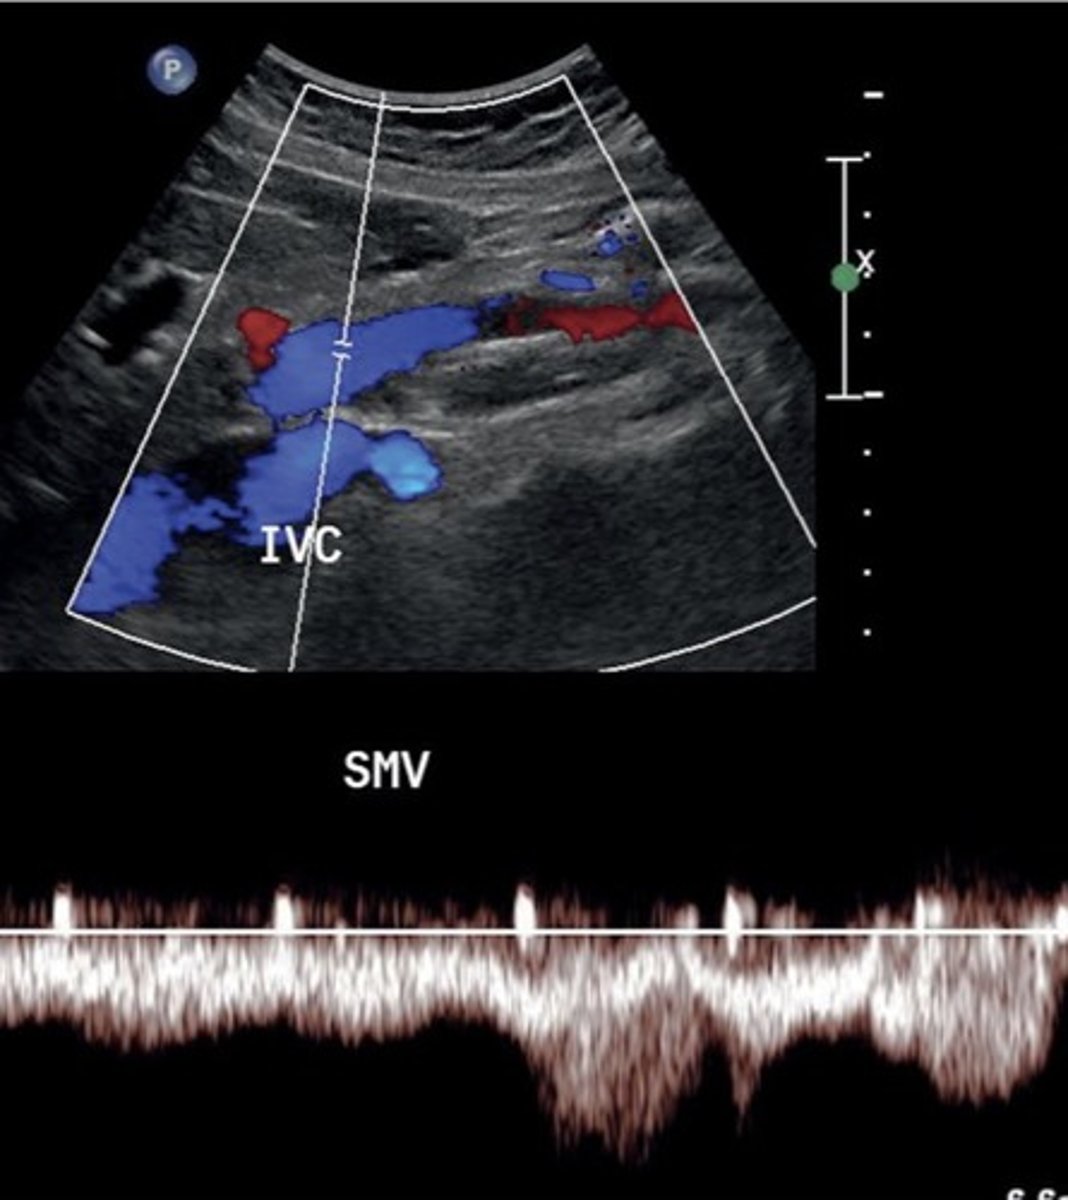

SMV Doppler Waveform

Hepatopetal flow

Continuous monophasic with slight respiratory variation